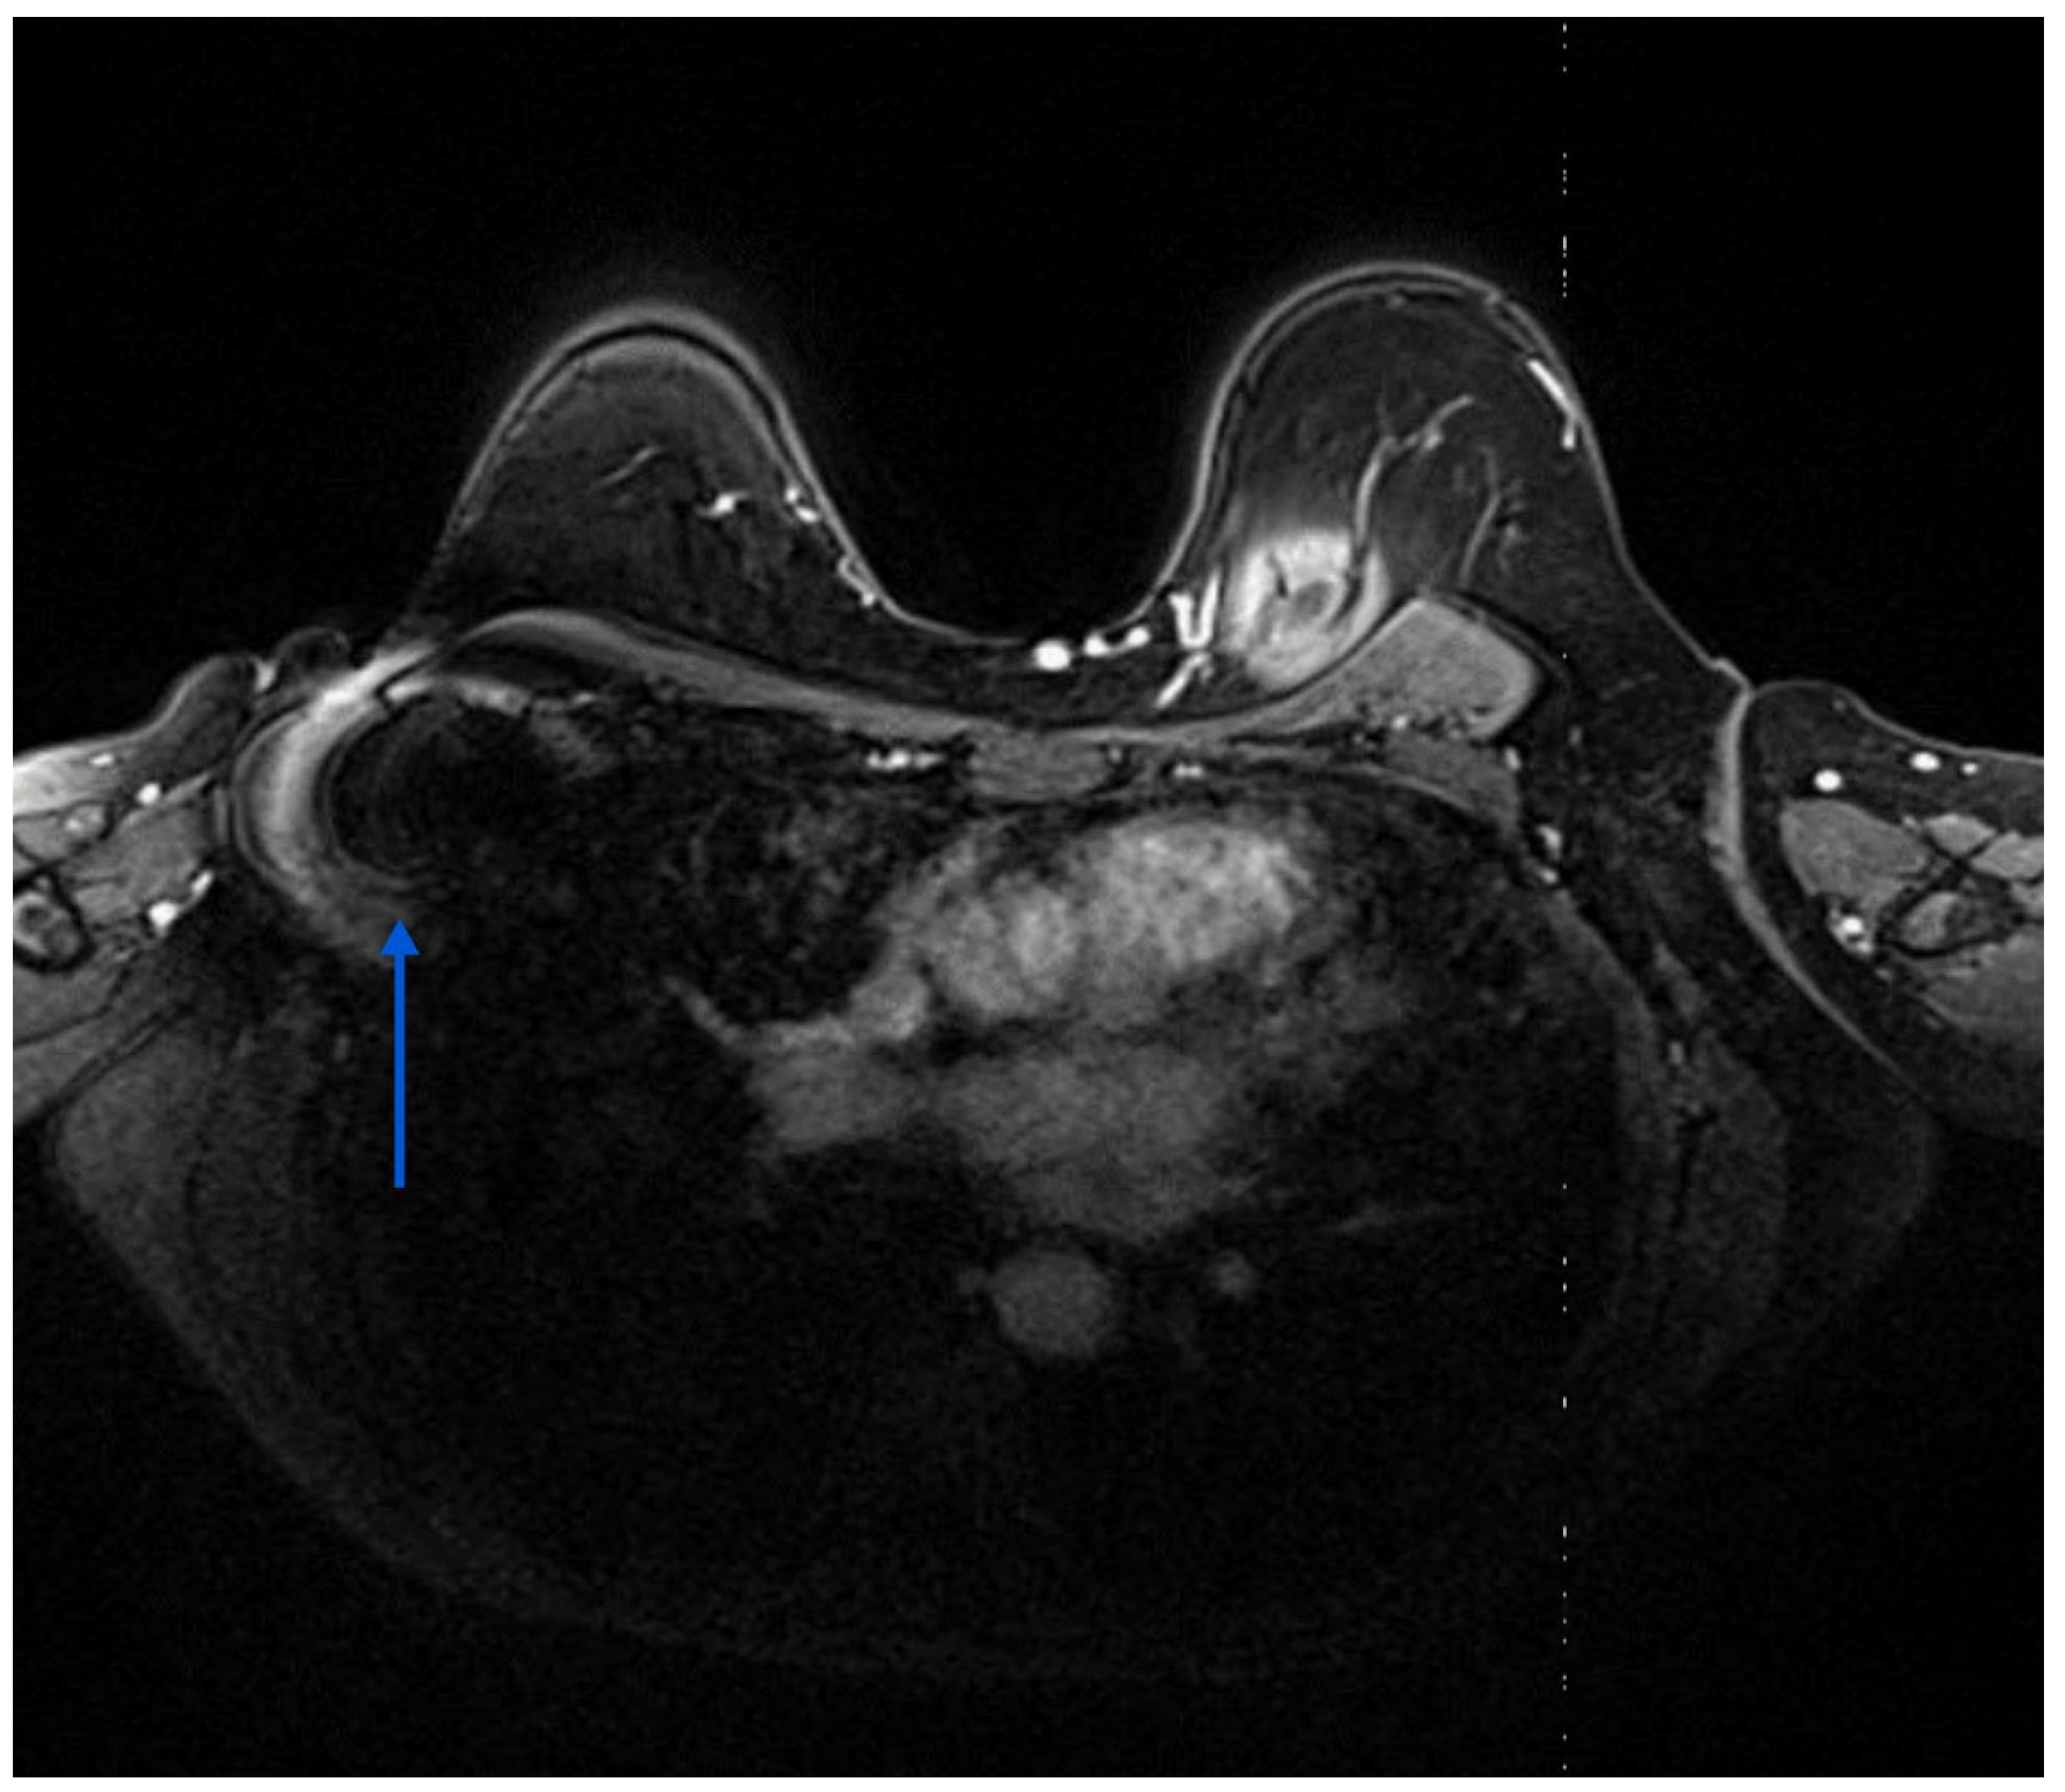

4.2. RRL versus Other Wire-Free Localisation Technologies

4.3. Imaging Modalities for Axillary Monitoring

Figure 6. Breast MRI showing a small artefact indicated by an arrow in (4.5 mm in size) in the left axilla related to the Savi Scout reflector within a normal-looking lymph node, suggesting a complete radiological response post-NST. The MRI void signal is significantly smaller than that associated with Magseed demonstrated in Figure 3.